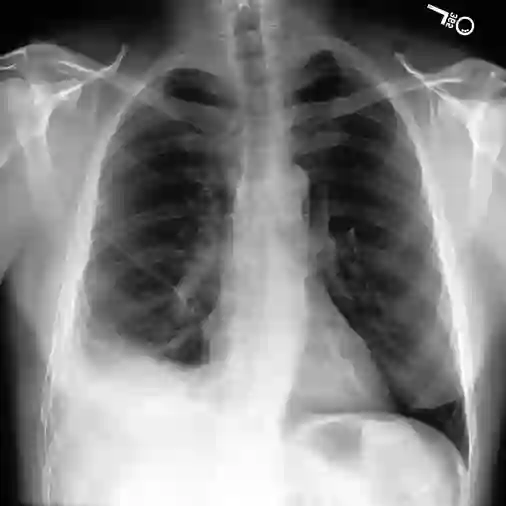

The latest breakthroughs in large vision-language models, such as Bard and GPT-4, have showcased extraordinary abilities in performing a wide range of tasks. Such models are trained on massive datasets comprising billions of public image-text pairs with diverse tasks. However, their performance on task-specific domains, such as radiology, is still under-investigated and potentially limited due to a lack of sophistication in understanding biomedical images. On the other hand, conversational medical models have exhibited remarkable success but have mainly focused on text-based analysis. In this paper, we introduce XrayGPT, a novel conversational medical vision-language model that can analyze and answer open-ended questions about chest radiographs. Specifically, we align both medical visual encoder (MedClip) with a fine-tuned large language model (Vicuna), using a simple linear transformation. This alignment enables our model to possess exceptional visual conversation abilities, grounded in a deep understanding of radiographs and medical domain knowledge. To enhance the performance of LLMs in the medical context, we generate ~217k interactive and high-quality summaries from free-text radiology reports. These summaries serve to enhance the performance of LLMs through the fine-tuning process. Our approach opens up new avenues the research for advancing the automated analysis of chest radiographs. Our open-source demos, models, and instruction sets are available at: https://github.com/mbzuai-oryx/XrayGPT.